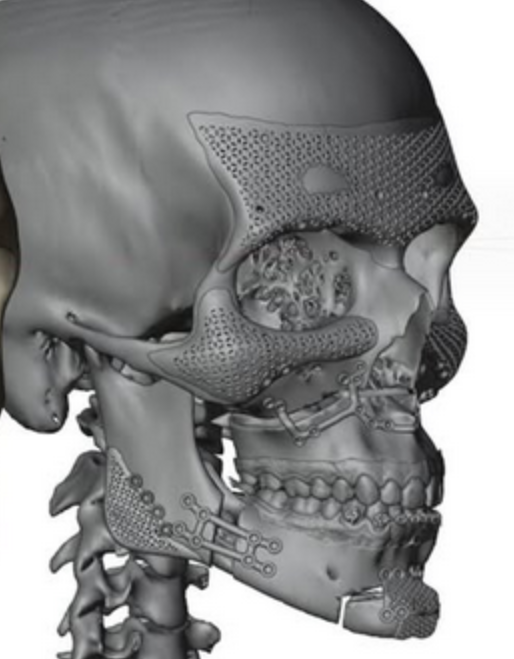

I paypigged for faceiq labs mostly because I want objective statistics for all the autistic craniofacial measurements so I can make plans for surgery etc. I actually made a similar program myself but it only has 16 measurements and only does front profile so this is definitely more comprehensive.

I put in both my current face and a morphed version including ideal surgical changes (more details later) and the results I got are very interesting. For the most part most of my problems can be solved by adding to the face, either through advancement or implants. My FWHR/midface ratio is good and IPD is wide but accomodates for facial width increase which would bring other ratios into harmony.

After morphing the front and side to add a trimax (+msdo?), jaw angle implants, infraorbital-malar implants & supraorbital advancement (implants/filler/grafting) I got these scores. I tried to be as realistic as possible with the morphs and didn't change anything that is not possible with surgery.

As you can see above my side profile literally goes from sub5 to a 9 in harmony when my jaw angle and recession is fixed which is possible with trimax + implants. My front profile becomes 8.49/10, I was slightly conservative with jaw changes (increased bigonial width from 78% to 85% while ideal would be 88%) so I could potentially score even higher but I'm trying to be realistic.

After morphing the front and side to add a trimax (+msdo?), jaw angle implants, infraorbital-malar implants & supraorbital advancement (implants/filler/grafting) I got these scores. I tried to be as realistic as possible with the morphs and didn't change anything that is not possible with surgery.

As you can see above my side profile literally goes from sub5 to a 9 in harmony when my jaw angle and recession is fixed which is possible with trimax + implants. My front profile becomes 8.49/10, I was slightly conservative with jaw changes (increased bigonial width from 78% to 85% while ideal would be 88%) so I could potentially score even higher but I'm trying to be realistic.